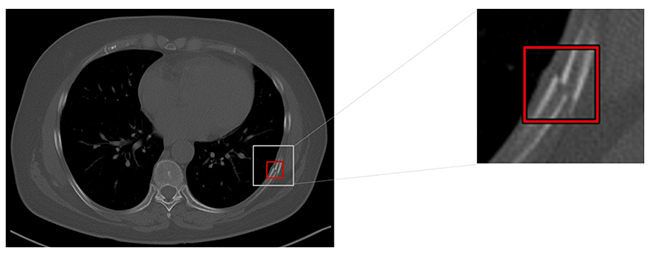

(2)「VR機能」と併用することで,肋骨骨折箇所を俯瞰して観察することができる。例えば,救急外来などで重度の外傷患者に対して本機能を使用することで,詳細な読影が可能となり,どの方向から外傷を受けたかなどを推測する一助になり,骨折の原因分析などを支援する。

「VR機能」と併用した時の検出イメージ